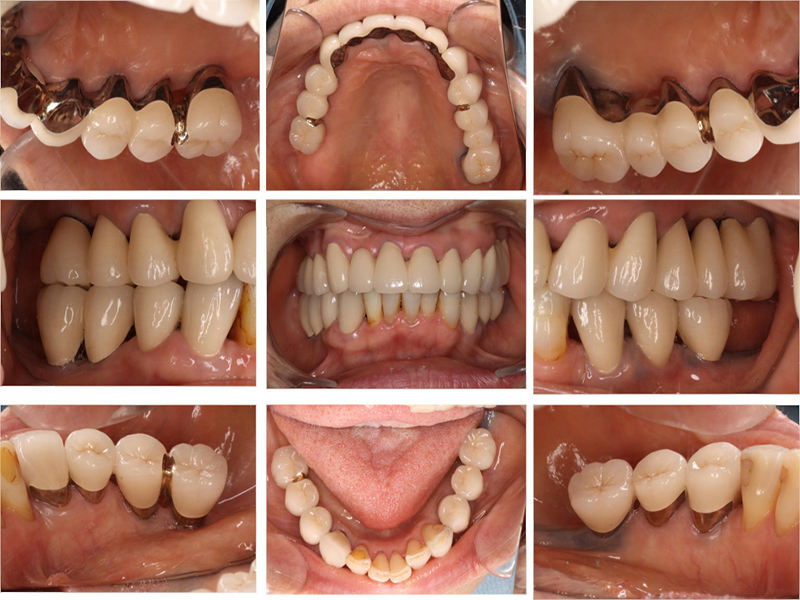

治療後の口腔内写真